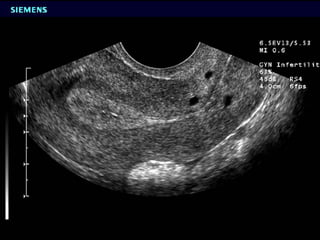

Congenital Uterine Anomaly n Diagnosis: History Pelvic exam Hysterosalpingography U/S MRI Laproscopy Hysteroscopy IVP or U/S (Exclude Renal anomaly )

Congenital Uterine Anomaly n Precise incidence is unknown (range from 1-2 %) n  Clinical presentation: 1 Usually asymptomatic 2 Menstrual disorder 3 Dysmenorrhea 4 Recurrent abortion ( decrease intrauterine volume and vascularity, increase uterine irritability and cervical incompetance ) 5 Premature labor 6 Abnormal presentation 7 Primary infertility